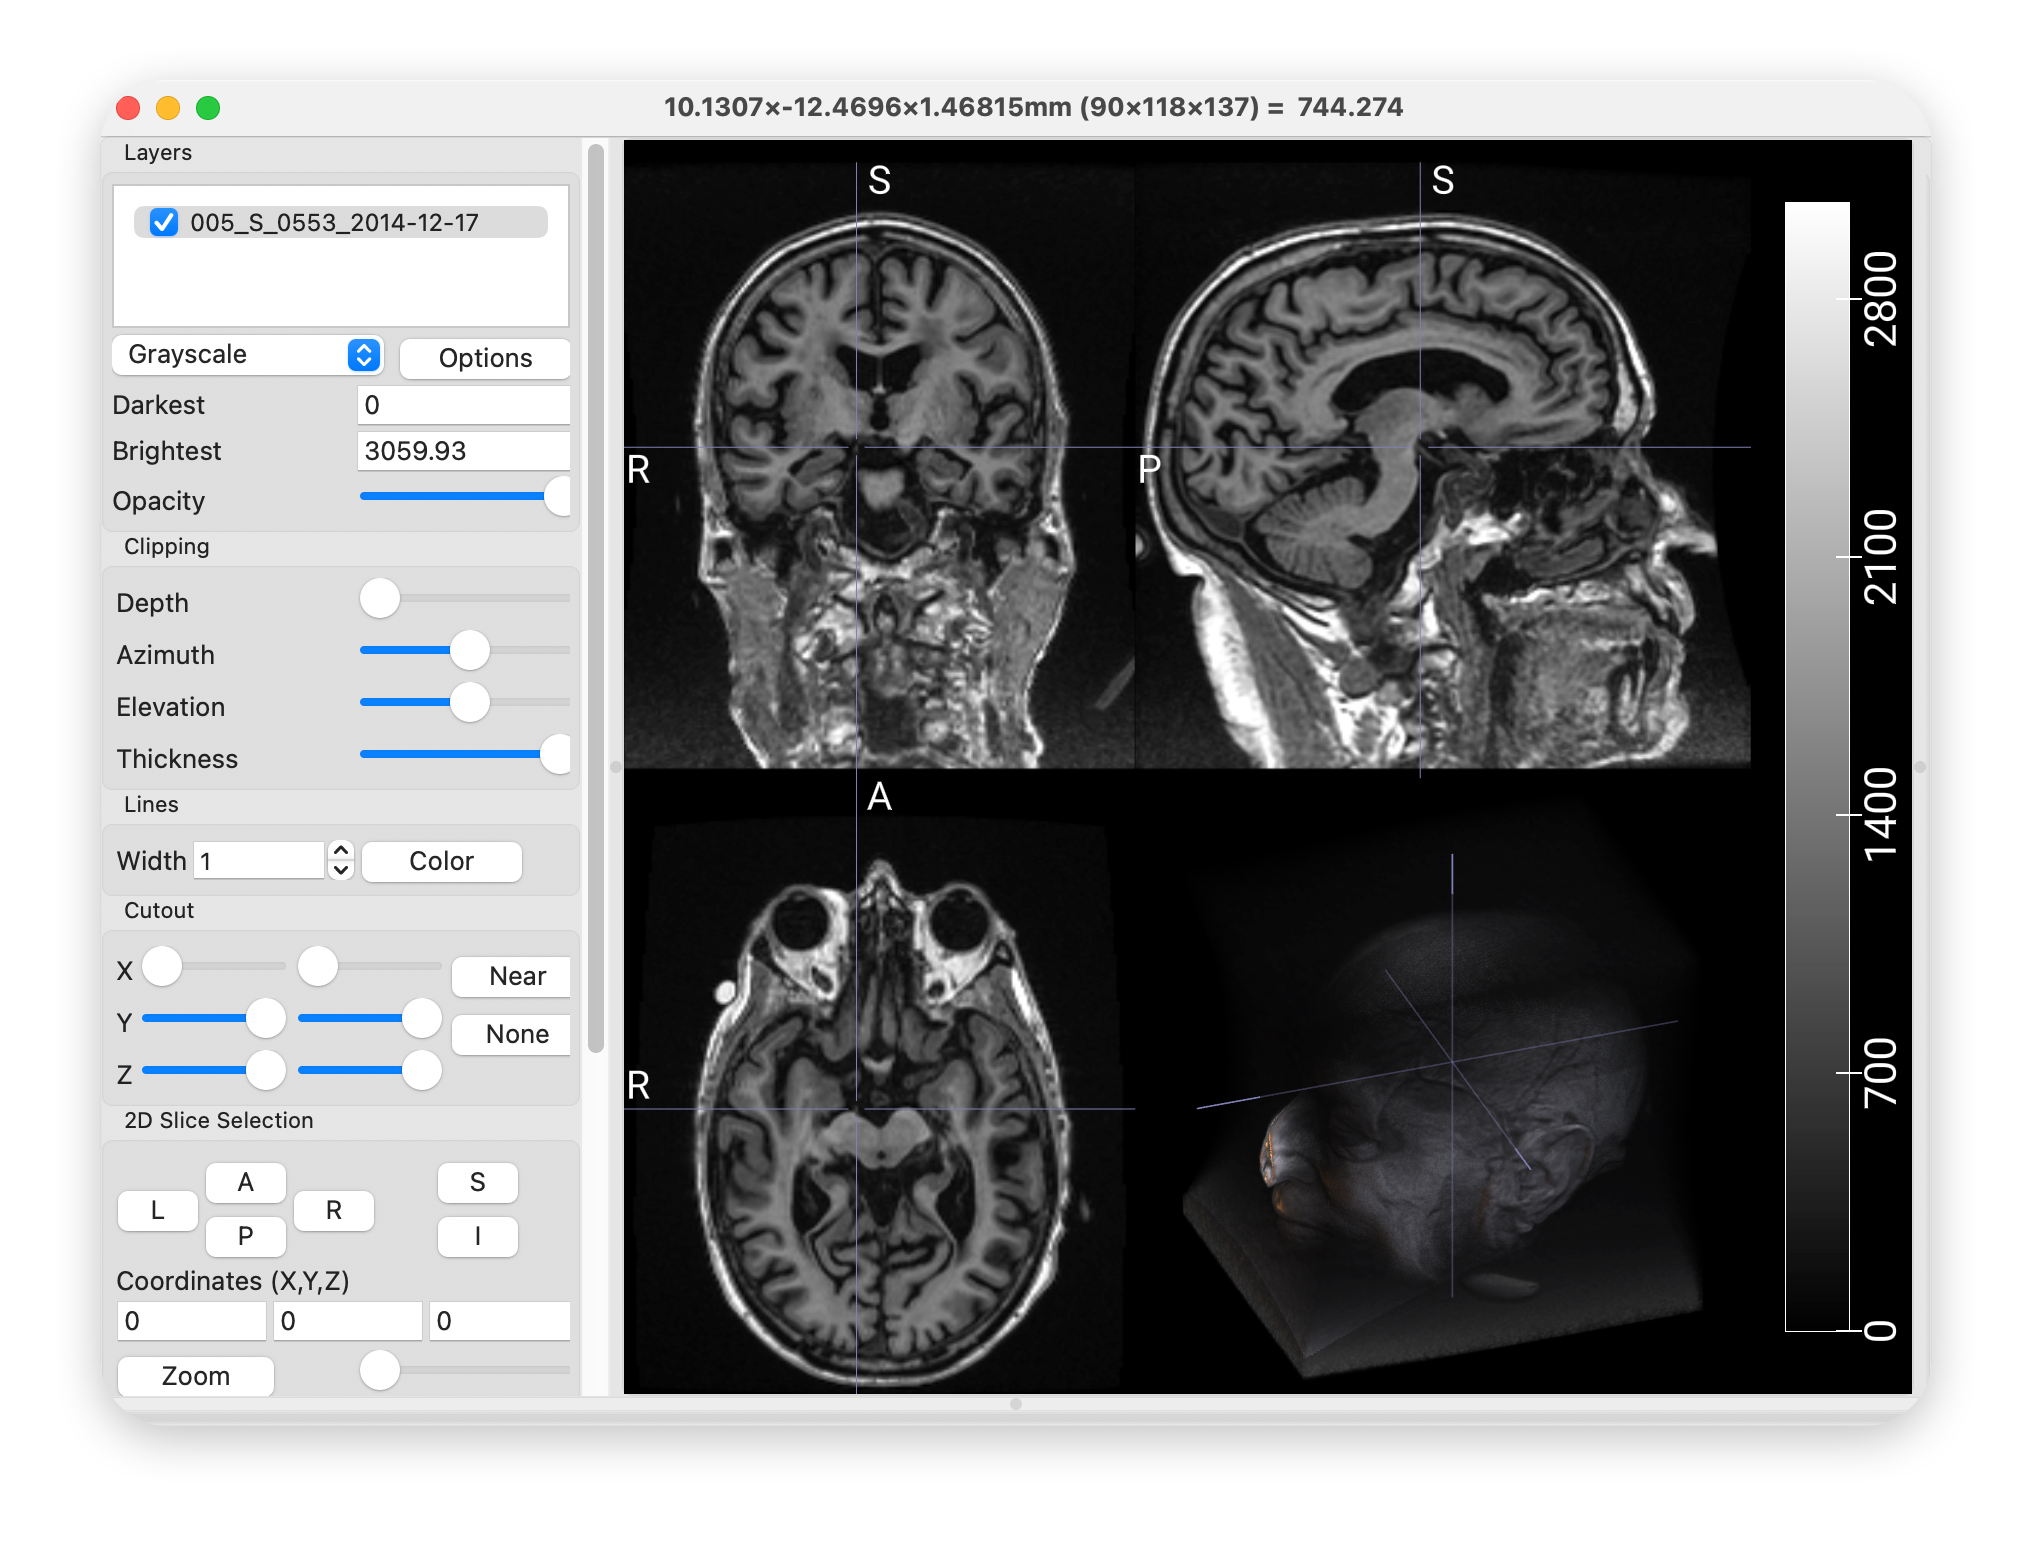

MRI源文件

hd-bet -i INPUT_FOLDER -o OUTPUT_FOLDER4.输出图像

shutil.copy(t, save_path)8.输出图像